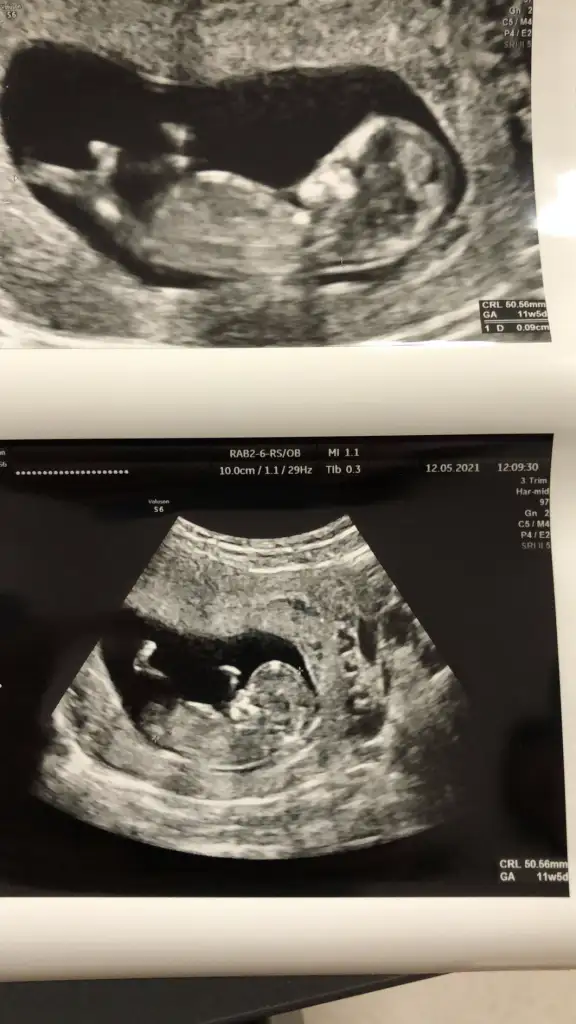

Emin olmadım ama sanki kız gibi geldi banaMerhaba arkadaslar,aslinda bebegimin cinsiyeti belli,dr.eşime kağıda yazıp verdi ama eşim pazar gunu surpriz yapacagi icin bana søylemiyor,sizin bi tahmininiz varmı?Merakdan çatliyorum.Eki Görüntüle 2848569

Canım şimdi doktordan çıktık bildin erkekmisErkek görünüyor

Valla bravo arkadaşım,az ønce øgrendim, Allahin izniyle zillim geliyorEmin olmadım ama sanki kız gibi geldi banaen iyi 11 12 13 haftalar olmalı yada başka USG varsa paylaşın

Sağlıkla gelsin oğlusun

Sağlıkla gelsin prensesValla bravo arkadaşım,az ønce øgrendim, Allahin izniyle zillim geliyor⚘⚘⚘